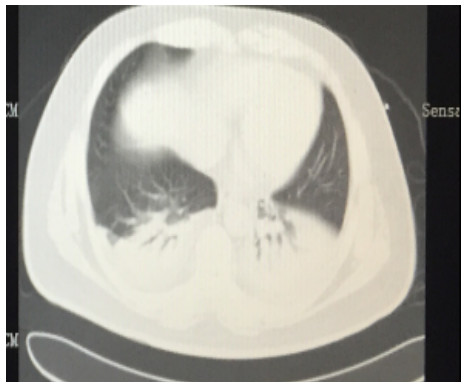

SAP发生呼吸衰竭的原因很复杂,其原因有以下几种。(1)SAP因为炎症反应导致的ARDS(图 1),这是普遍认为的一种原因,但实际上ARDS在SAP患者呼吸衰竭中很多时候是非主要原因。SAP急性期虽然病情进展很快,出现多脏器功能损伤,甚至休克,有类似于脓毒症和感染性休克样的表现,但其炎症反应并不如脓毒症这么强烈,大量的研究可见SAP发生过程其IL-6很少过千,而脓毒症则IL-6动辄大于5 000或10 000,SAP两肺影像学也很少有典型的非心源性肺水肿的双侧阴影,超声下也很少有“B线”表现。但胆道感染引起的脓毒症合并SAP的患者,其ARDS发生率会明显上升。现在随着高脂血症胰腺炎的增加,部分患者到院时同时存在糖代谢障碍,合并有糖尿病酮症,入院前后出现糖尿病酮症昏迷,有些患者会伴有呕吐误吸或者插管时误吸,这类患者在急性期会出现误吸相关的ARDS。(2)SAP是腹腔重症的一种,急性期因为腹膜后急性胰周液体积聚和急性胰周坏死物积聚,导致腹腔压力进行性升高,随之出现横膈抬高,两肺压缩,从而导致“小肺”,这和ARDS的“baby lung(小肺)”不同(图 1: ARDS;图 2、3: 腹内压14 mmHg和23 mmHg的对比,明显看到图 3呈现横膈抬高引起的小肺)。因横膈位置上抬导致小肺是SAP呼吸衰竭的主要原因。(3)两下肺不张(图 4)和胸腔积液(图 5):这两个原因也是导致SAP呼吸衰竭的主要原因,因为膈下刺激,导致两下肺的不张和大量胸腔积液常见于SAP患者,这两种原因导致的呼吸衰竭也和ARDS不同。(4)其他原因:胸腔出血、肺梗死和气胸亦可见于SAP相关呼吸衰竭,但相对少见。

| 图 4 肺不张 |